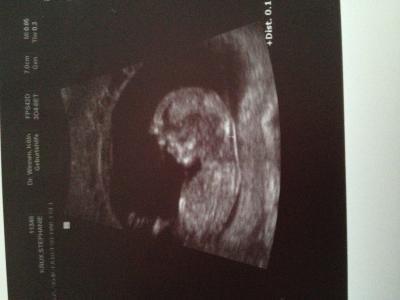

Hatten gestern die Nackenfaltnessung! Alles soweit ok, Nackenfalte 1,2 cm! Er hat sich richtig Zeit gelassen und ca 10 mal gemessen! Wenn das Baby gut liegt müssen wir das ausnutzen waren seine Worte;-) gerne Herr Doktor;-) Baby ist ssl 5,7 cm! Geschlecht in 3 Wochen!

Bild zu Gestern ntm alles gut - Forum für Mai - Mamis